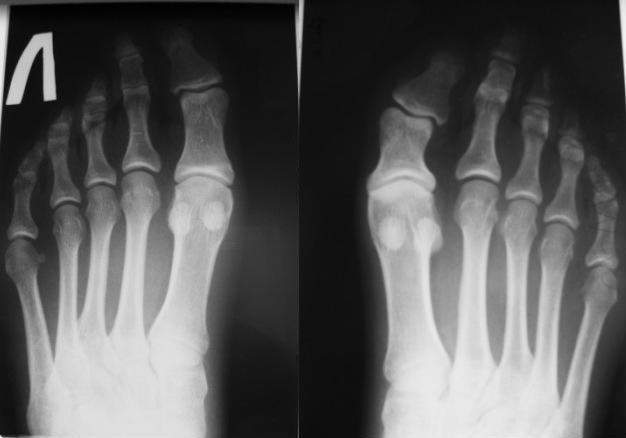

Re: Дисплазия фаланги пальца стопы

Рентгенограммы прилагаю.